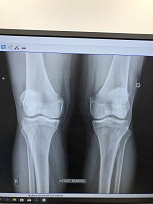

I would love to be baggin but I took a fall last week. I fell last week landscaping and hurt my leg. I went to doctor yesterday and he took X-ray’s of my knees. Luckily nothing is broken. Now I have to go for MRI on Friday to see if there is any damage to my quadricep.ugh can’t really stand for to long with out pain. Being careful not to damage it any further. Will know more next week when doctor checks out MRI.Then I can go from there. I have been reading my speedbagbible and reading every post of this great forum while sitting in recliner.I am pretty active so this sitting around really sucks.I just sit here going through speedbag bible techniques punching in air. Wife thinks I’m crazy.hope to be under the board soon.